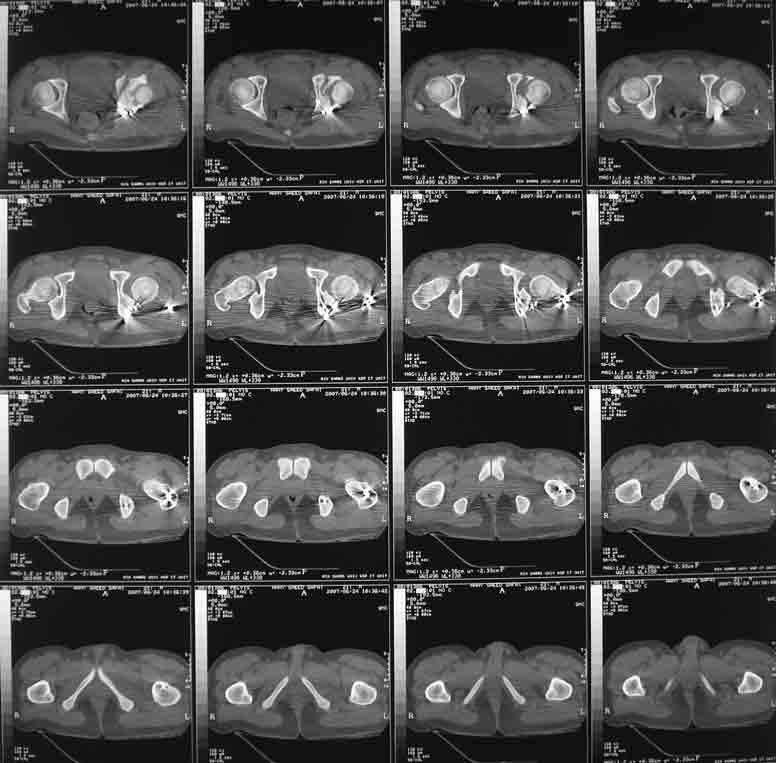

This is a 20 year old man who had an irreducible fracture dislocation of the left acetabulum, associated transverse + posterior wall type, operated nearly 2 weeks following the trauma.

Open reduction and internal fixation was performed through posterior approach with trochanteric osteotomy. Extraction of the incarcerated fragment was very difficult, and then reduction of the femoral head also felt less easy than usual. After plate fixation, the head was found to subluxe on maximum internal rotation. However, it became more or less stable after fixation of the trochanteric osteotomy and reattachment of the rotators. Xray showed lateral displacement of the femoral head. CT was also performed and it confirmed the lateral displacement although I don't know if it could be termed subluxation. The flexion- extension ROM is 0-45 with some internal-external rotation, but the limitation is mostly by pain. I cannot explain this situation and would you like to hear your suggestions.

I am confident that I left no intraarticular fragments. Could the comminution in the anterior wall visible on CT be responsible for this?

I am planning to fix his concomitant tibia fracture within 3 days, and in the process perform an examination under anaesthesia. If the ROM is good, I may leave him alone. What do you think? I am sending the x ray and CT in 3 mails